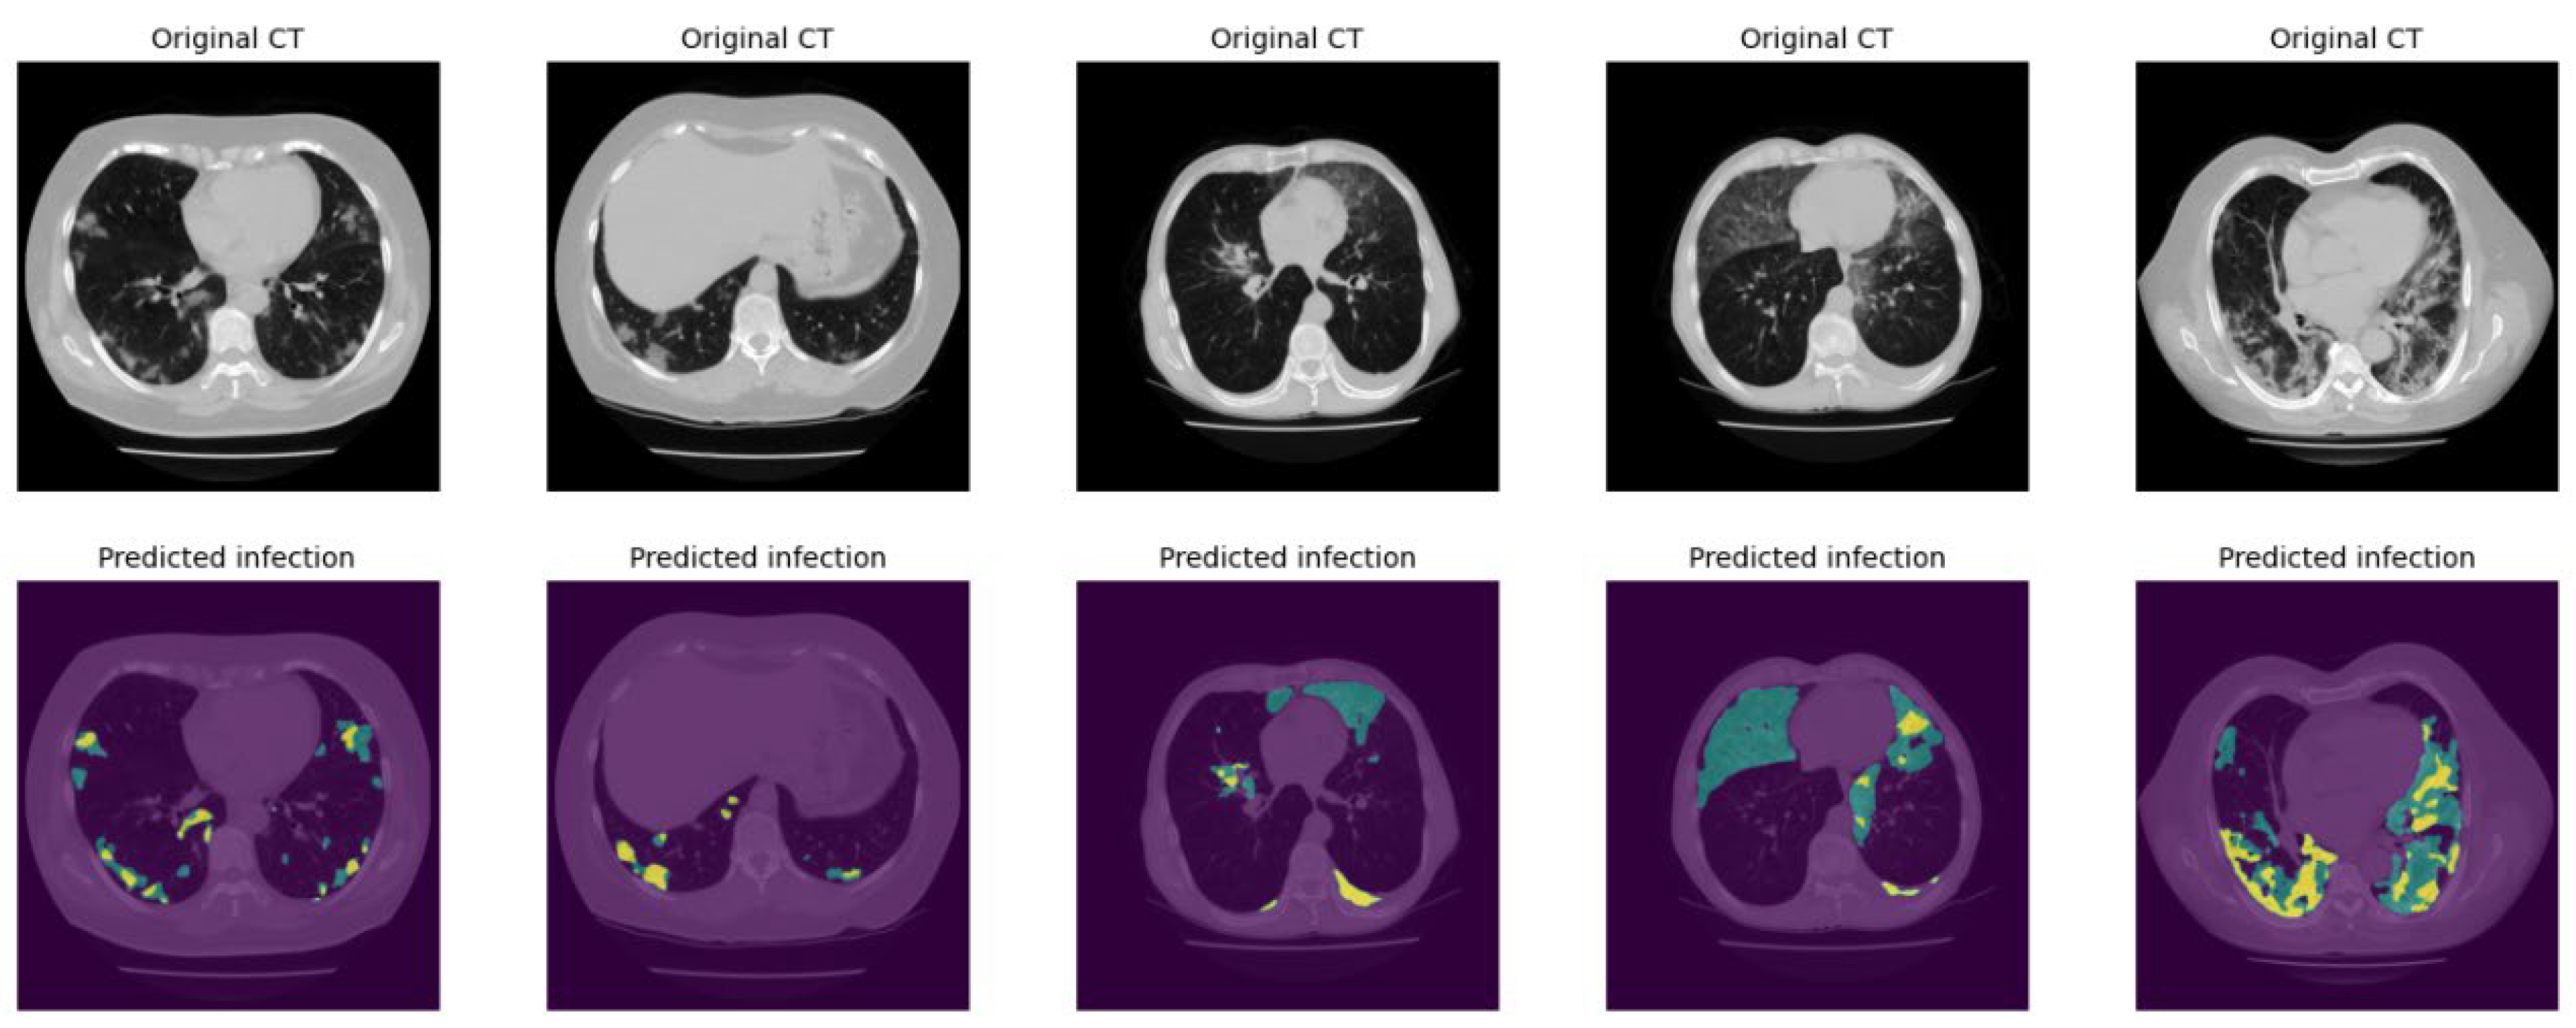

Figure 7 demonstrates several examples of the lung and infection segmentation results. The left column illustrates the raw CT images while the second and third columns illustrate the masks of the segmented lung and disease infection areas, respectively. In addition, Figure 8, shows the patch segmentation results of GGO and consolidation areas (or blobs).

Figure 8. Patch segmentation results. The green area represents the GGO and Crazy Paved pattern. The yellow area shows the Consolidation area.